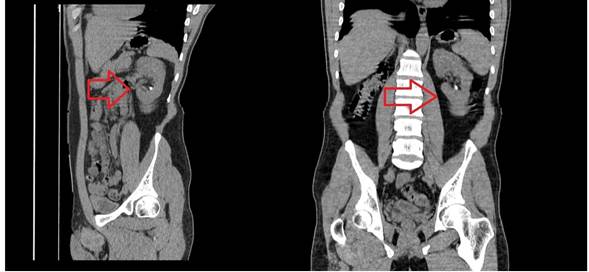

A la exploración con signos dudosos de irritación peritoneal. Por lo que se indica manejo sintomático y realización de Urotac. Éste revelo que el riñón derecho se encontraba hacia la pelvis con presencia de múltiples cálculos (Fig. 1), el riñón izquierdo era de localización normal, por lo que se interconsulta al servicio de Urología (Fig. 2).

Fig. 2 Riñón izquierdo de forma, tamaño y localización normal.